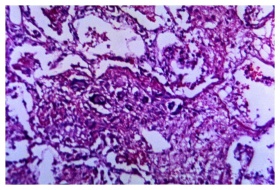

A 125X photomicrograph magnification of a hematoxylin and eosin (H&E)–stained lung tissue specimen, revealed the presence of cytoarchitectural changes indicative of a blastomycosis fungal infection. Original image sourced from US Government department: Public Health Image Library, Centers for Disease Control and Prevention. Under US law this image is copyright free, please credit the government department whenever you can”.